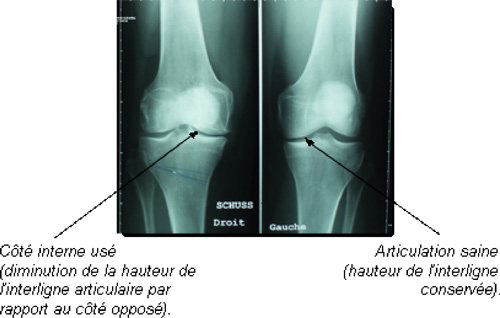

L’ostéotomie tibiale de valgisation est un des traitements chirurgicaux de la gonarthrose, surtout de la gonarthrose médiale (interne). Elle est réalisée pour traiter l’arthrose d’un seul compartiment du genou lorsque la prothèse totale du genou n’est pas indiquée et lorsqu’on peut se passer de prothèse uni-compartimentale.

L’ostéotomie tibiale de valgisation a pour but de rééquilibrer l’axe du membre inférieur et donc les pressions au niveau de l’articulation fémoro-tibiale du genou.

Le but de l’ostéotomie tibiale de valgisation est de transformer un génu-varum (jambe arquée) en génu-valgum afin de diminuer les contraintes du côté usé et de les reporter sur le côté sain, c’est-à-dire sur le côté externe en cas d’arthrose fémoro-tibiale interne. On ne remplace donc pas le côté usé mais on diminue très fortement les douleurs grâce à la diminution des sollicitations en pression et en retardant l’usure on retarde également la mise en place d’une prothèse du genou.